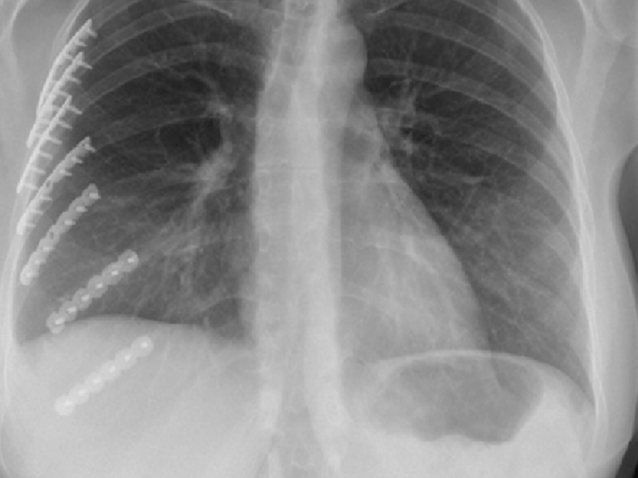

갈비뼈의 미세 손상은 단순 엑스레이(X-ray)로 잘 보이지 않는 경우가 많습니다. 이 경우 CT(컴퓨터 단층촬영) 또는 초음파 검사가 보조적으로 사용될 수 있습니다. 의사는 병력 청취와 촉진검사를 통해 통증 부위를 확인한 뒤, 필요한 경우 정밀 진단을 권합니다.